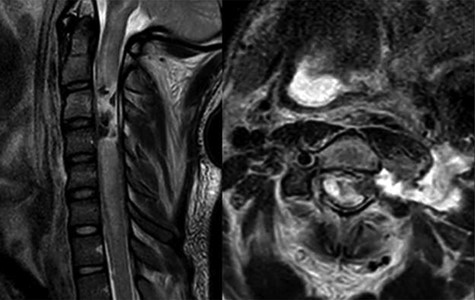

A 24-year-old African–American male presented with a gunshot wound through the left face and neck. On exam the patient was noted to be pulseless and apneic. After resuscitation, initiation of a mass transfusion protocol and return of spontaneous circulation, the patient was GCS 11 (E4V1TM6) and was noted to have no movement in any extremities. A computed tomographic (CT) cervical spine scan and CT angiography of the neck revealed a bullet trajectory through the left C2–3 facet with fractured c3 posterior elements and a bullet fragment at the C3 level, a left vertebral artery dissection, and left internal and external carotid artery transections (Fig. 1). The patient underwent an emergent tracheostomy, neck exploration, left ICA/ECA ligation and partial wound closure. This was followed by endovascular embolization of the left vertebral artery. The patient was noted to have serosanginous drainage from the neck wound consistent with a CSF leak. After an unsuccessful trail of conservative management, a lumbar drain was placed and confirmed with fluoroscopic guidance without CSF egress. A magnetic resonance imaging (MRI) scan of the cervical spine was obtained which demonstrated a pronounced CSF fistula and a complete obstruction of the CSF space at the C3–6 levels (Fig. 2).

CT angiogram of the neck demonstrates a bullet trajectory through the left C2–3 facet with fractured c3 posterior elements and bullet and bony fragments within the canal at the C3–4 level; left: sagittal view; right: axial view.

MRI T2 weighted sequence sagittal (left) and axial (right) at the c3 level demonstrates severe spinal cord damage, canal obliteration from c3 to c6 and a large left sided csf fistula at the C3 level.